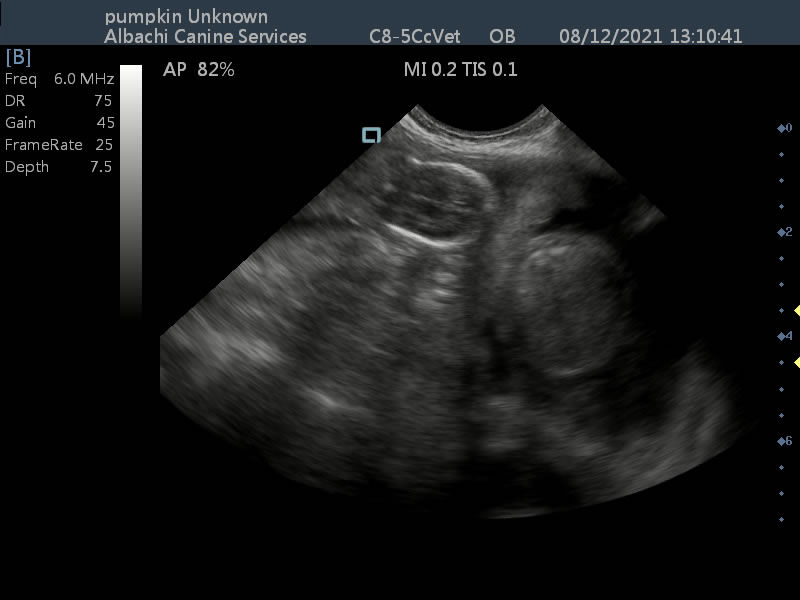

Fourth scan for Pumpkin the Chihuahua.